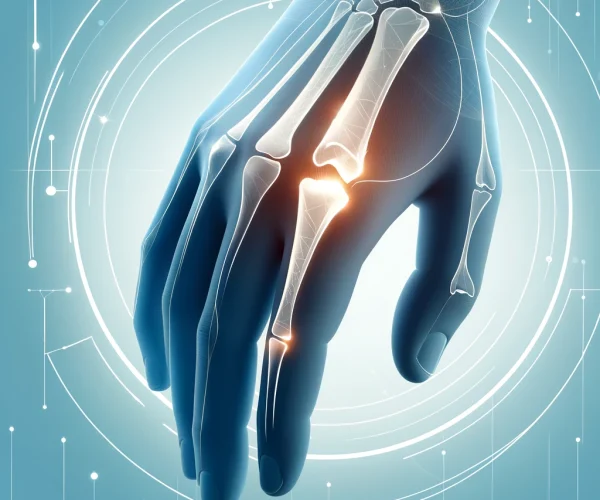

Hand and wrist fractures occur when one or more bones in these areas break due to direct impact or excessive force. Common types of fractures include:

- Finger Fractures: Breaks in the bones of the fingers.

- Metacarpal Fractures: Breaks in the bones of the hand.

- Distal Radius Fractures: Breaks in the end of the forearm bone near the wrist.